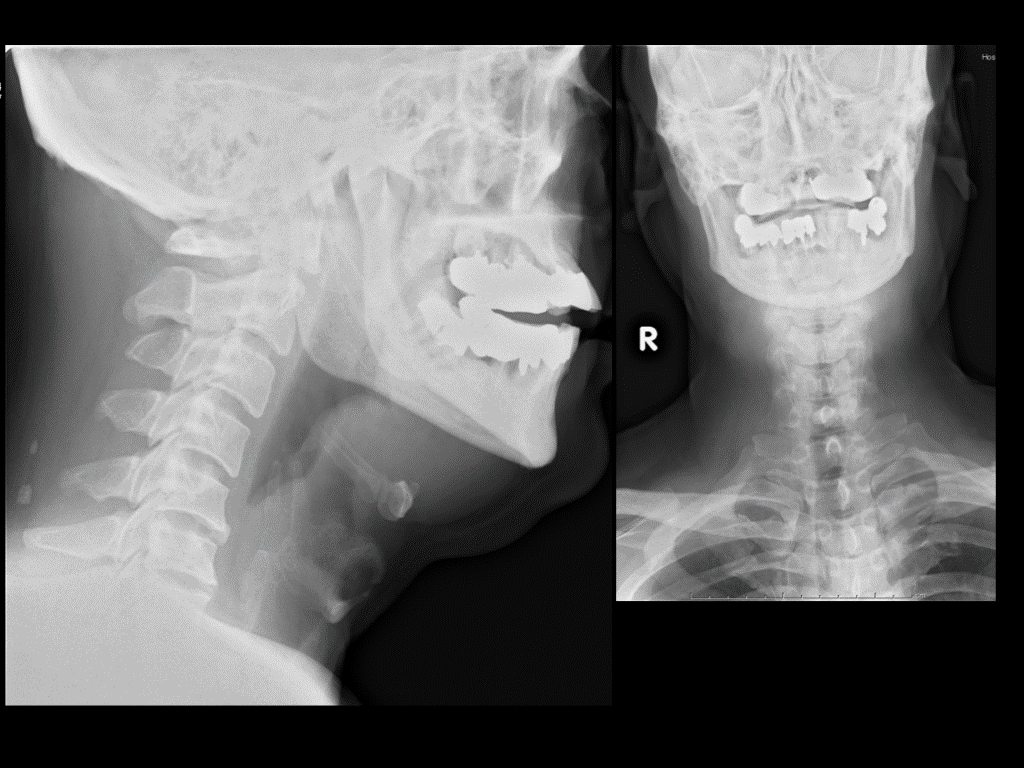

頸部側面レントゲン 原典不明

頸部側面写真  ABCD  3×7=21

喉頭蓋炎の画像 USでの評価も試みられている J of Gen and Family Med. 2020